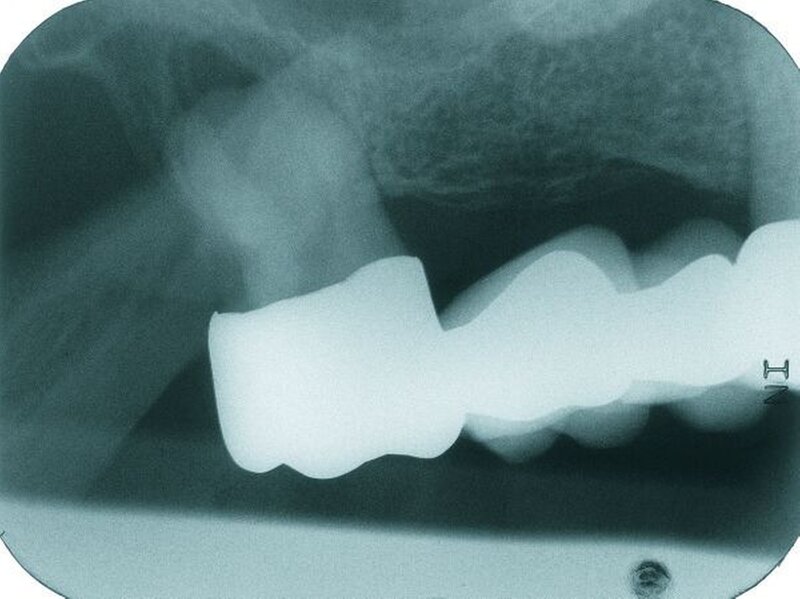

Auf dem vor Anfertigung des Zahnersatzes angefertigten OPG sowie den angefertigten Zahnfilmen der regiones 17 und 27 waren generalisierte horizontale Knochenverluste im Bereich aller verbliebenen Zähne erkennbar. Die Zähne 17 und 27 wiesen zudem vertikale Knocheneinbrüche auf. Eine radiologische Furkationsbeteiligung ließ sich in beiden Fällen nachweisen. Der Zahn 47 war wurzelkanalgefüllt.

Obwohl der Zahn 47 eine radiologisch nicht vollständig bis zum radiologischen Apex reichende Wurzelfüllung aufwies, wurde auf eine Revision der Wurzelfüllung aufgrund einer seit mehr als 15 Jahren bestehenden Beschwerdefreiheit des Patienten und vollständiger Symptomlosigkeit des Zahnes verzichtet [Peak et al., 1994]. Der Patient wurde über diese Sachverhalte ausführlich aufgeklärt und erklärte sich mit dem Belassen der Wurzelfüllung einverstanden.